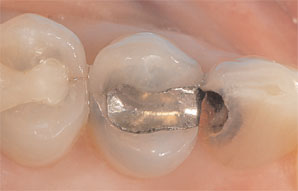

Once this image was captured, the restoration was then designed chairside. Using the E4D DentaLogic™ software, a proposed model for the restoration was created. At this point, the operator began by properly aligning the model (e.g., path of insertion) and then identifying the margin. The software automatically aligned the bitestrip image and preparation image using the data scanned from the adjacent teeth; there was no need to be concerned about camera alignment between models (Case 1, Figure 3). The software then proposed a customized restoration from the database selected.